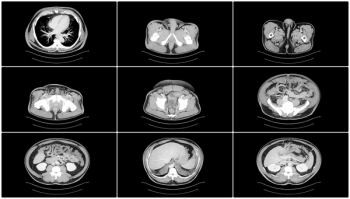

Greater imaging utilization has increased the prevalence of incidental findings or incidentalomas, but unclear clinical context and guidelines complicate management. Accordingly, these authors offer a thorough review of the literature and discuss new opportunities for improving interdisciplinary management strategies.